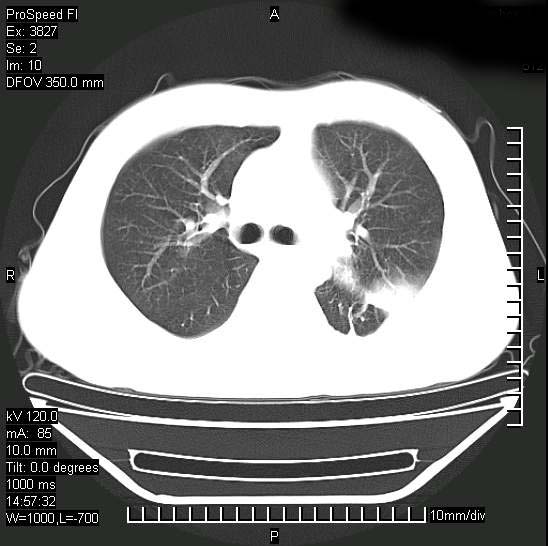

男性,一月前出现右侧肋区疼痛,较剧烈,干咳,无发热,自诉使用抗炎药后缓解,几天前又出现左侧剧烈疼痛,

发热,体温38。9,今天ct,考虑左侧包裹性脓胸,胸腔积液,右上中肺小斑片影,结核/炎症?胸水未见恶性细胞。